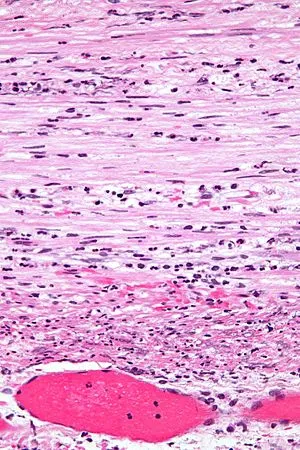

- Micro:

⭐ Neutrophilic infiltration of the muscularis propria is the pathognomonic histological hallmark.

- Edema, vascular congestion, mucosal ulceration, transmural inflammation and necrosis.